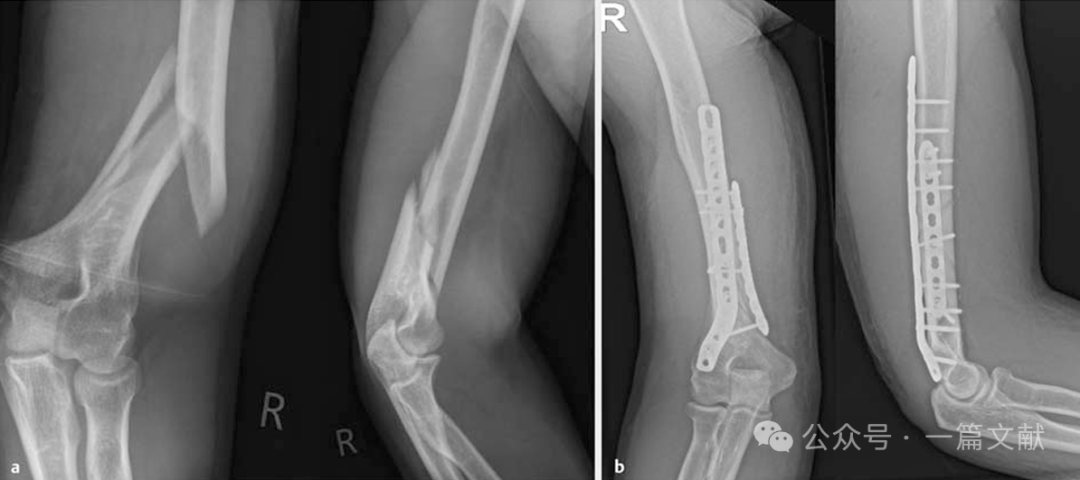

4.4 肱骨远端骨折:肱骨远端骨折的双钢板固定已成为临床实践中的标准手术方式。当前达成的共识是,A2型和A3型骨折以及所有C型骨折均应采用双钢板固定技术。建议选择不同长度的钢板,或者在使用相同长度的钢板时,避免同时拧入两块钢板最近端的螺钉。

关于两块钢板的分布方式仍存在争议。虽然平行放置在生物力学上具有优势,但在临床实践中尚未发现显著差异。同样,使用不同螺钉直径的各种钢板系统对手术结果也无显著影响。

如下图:45岁女性患者,肱骨远端骨折(AO 13C3型): 采用双锁定钢板固定,钢板呈90°放置。鹰嘴截骨术后通过钢丝张力带固定截骨部位。

4.5 尺骨鹰嘴或尺骨近端骨折:

尺骨近端骨折可采用不同的固定方式。简单骨折可通过钢丝张力带固定或标准背侧钢板固定。两种手术的功能结果相当,但由于软组织刺激,通常需要取出植入物。

对于更复杂的尺骨近端骨折,则更倾向于采用双钢板固定。背侧结合内侧的钢板或两侧钢板放置,可用锁定钢板(LCP)。也适用于Monteggia骨折或类似Monteggia损伤的治疗,以及尺骨近端骨折不愈合的翻修病例。